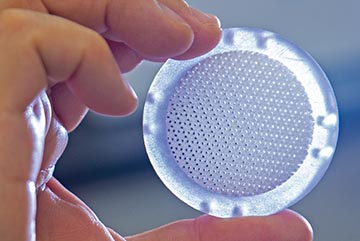

Through internally funded research, SwRI designed, developed and prototyped the bioreactor for T-cell and stem cell expansion. The patent-pending, disk-shaped design features tightly packed, interconnected spherical voids, providing a large surface-to- volume ratio for growing profuse quantities of cells. Its unique structure facilitates automatic control and delivery of nutrition and oxygen to cells.

Using a 3D commercial printer, we created production-ready bioreactors of different sizes with the same internal structure. This maintains the cell expansion process from discovery to development and manufacturing, reducing the costs involved to move into the commercialization phase. The device is made of a biocompatible material used in many FDA-cleared or -approved medical devices. Its low cost makes single-use bioreactors feasible.

SwRI’s patent-pending, disk-shaped bioreactor features tightly packed, interconnected spherical voids, providing a large surface-to-volume ratio for growing abundant quantities of cells.

Through internal funding, SwRI developed these novel, single-use bioreactors produced with 3D printing technology. Their unique structure is difficult if not impossible to fabricate using traditional injection molding techniques.

The unique structure of the new bioreactor is difficult to fabricate using traditional injection molding techniques. SwRI has developed a proprietary technology to produce the bioreactor with a smooth surface suitable for cell growth. We are currently establishing cleanroom fabrication and radiation sterilization procedures for the bio- reactor to meet the device quality and safety levels needed for clinical cell manufacturing.